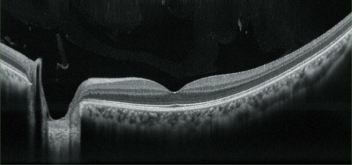

超高分辨率圖像

OCT成像時,平均提供多達50張圖像進行疊加,可根據實際情況,選擇超精細、精細和普通OCT敏感度。RS-330內置12兆像素CCD攝像頭,能夠提供高質量眼底圖像。

多種OCT掃描模式

本儀器提供多種掃描模式,醫生可根據視網膜區和眼科病理學,選擇合適的掃描模式。 視網膜:8種模式